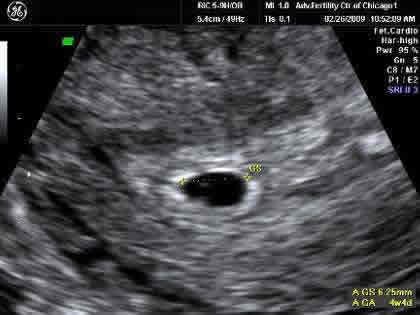

You may see the gestational sac in an ultrasound as early as 4 1/2 to 5 weeks . The gestational sac increases in diameter by 1 .13 mm per day and initially measures 2 to 3 mm in diameter, according . . .

Ultrasound at 5 weeks 5 days . e . ellabruniges . Jul 13, 2015 at 5:47 AM . i just came back from my first ultrasound with this pregnancy, and at 5 weeks 5 days, I've a 12 mm (mean sac measurement is 9mm) gestational sac but nothing else - no pole or yolk sac . I'm a little concerned as it was empty, but the doc didn't seem worried and said that it was . . .